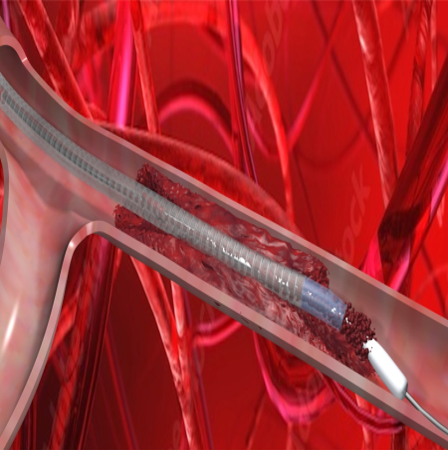

During most thrombectomy procedures, clinicians access the femoral artery or vein; track a catheter over a guidewire to the thrombi (blood clot) or emboli; and then apply suction with a syringe, aspirator, and/or electromechanical pump. Blood clot age, size, and location plus catheter size, type, shape, and aspiration force a

re important variables during thrombectomy. Electric pumps can aspirate fast, but are often associated with significant blood-loss.

“Electric pump-based thrombectomy systems can unexpectedly clog and/or remove 5 – 15ml per second of blood before removing blood clots,” said Dan Ryan, Board of Directors, VentiV Scientific Inc. “The Pulse is designed to instantly start, stop, increase, and/or decrease thrombectomy force at the tip, decrease clogging inside the catheter, and decrease blood-loss with use of any aspiration pump currently in the hospital.”